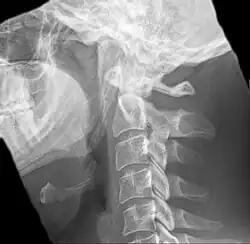

-

Radiograph, lateral view showing elongated stylohyoid process and stylohyoid ligament ossification -

Radiograph, lateral view showing joint-like formation in ossified stylohyoid ligament -